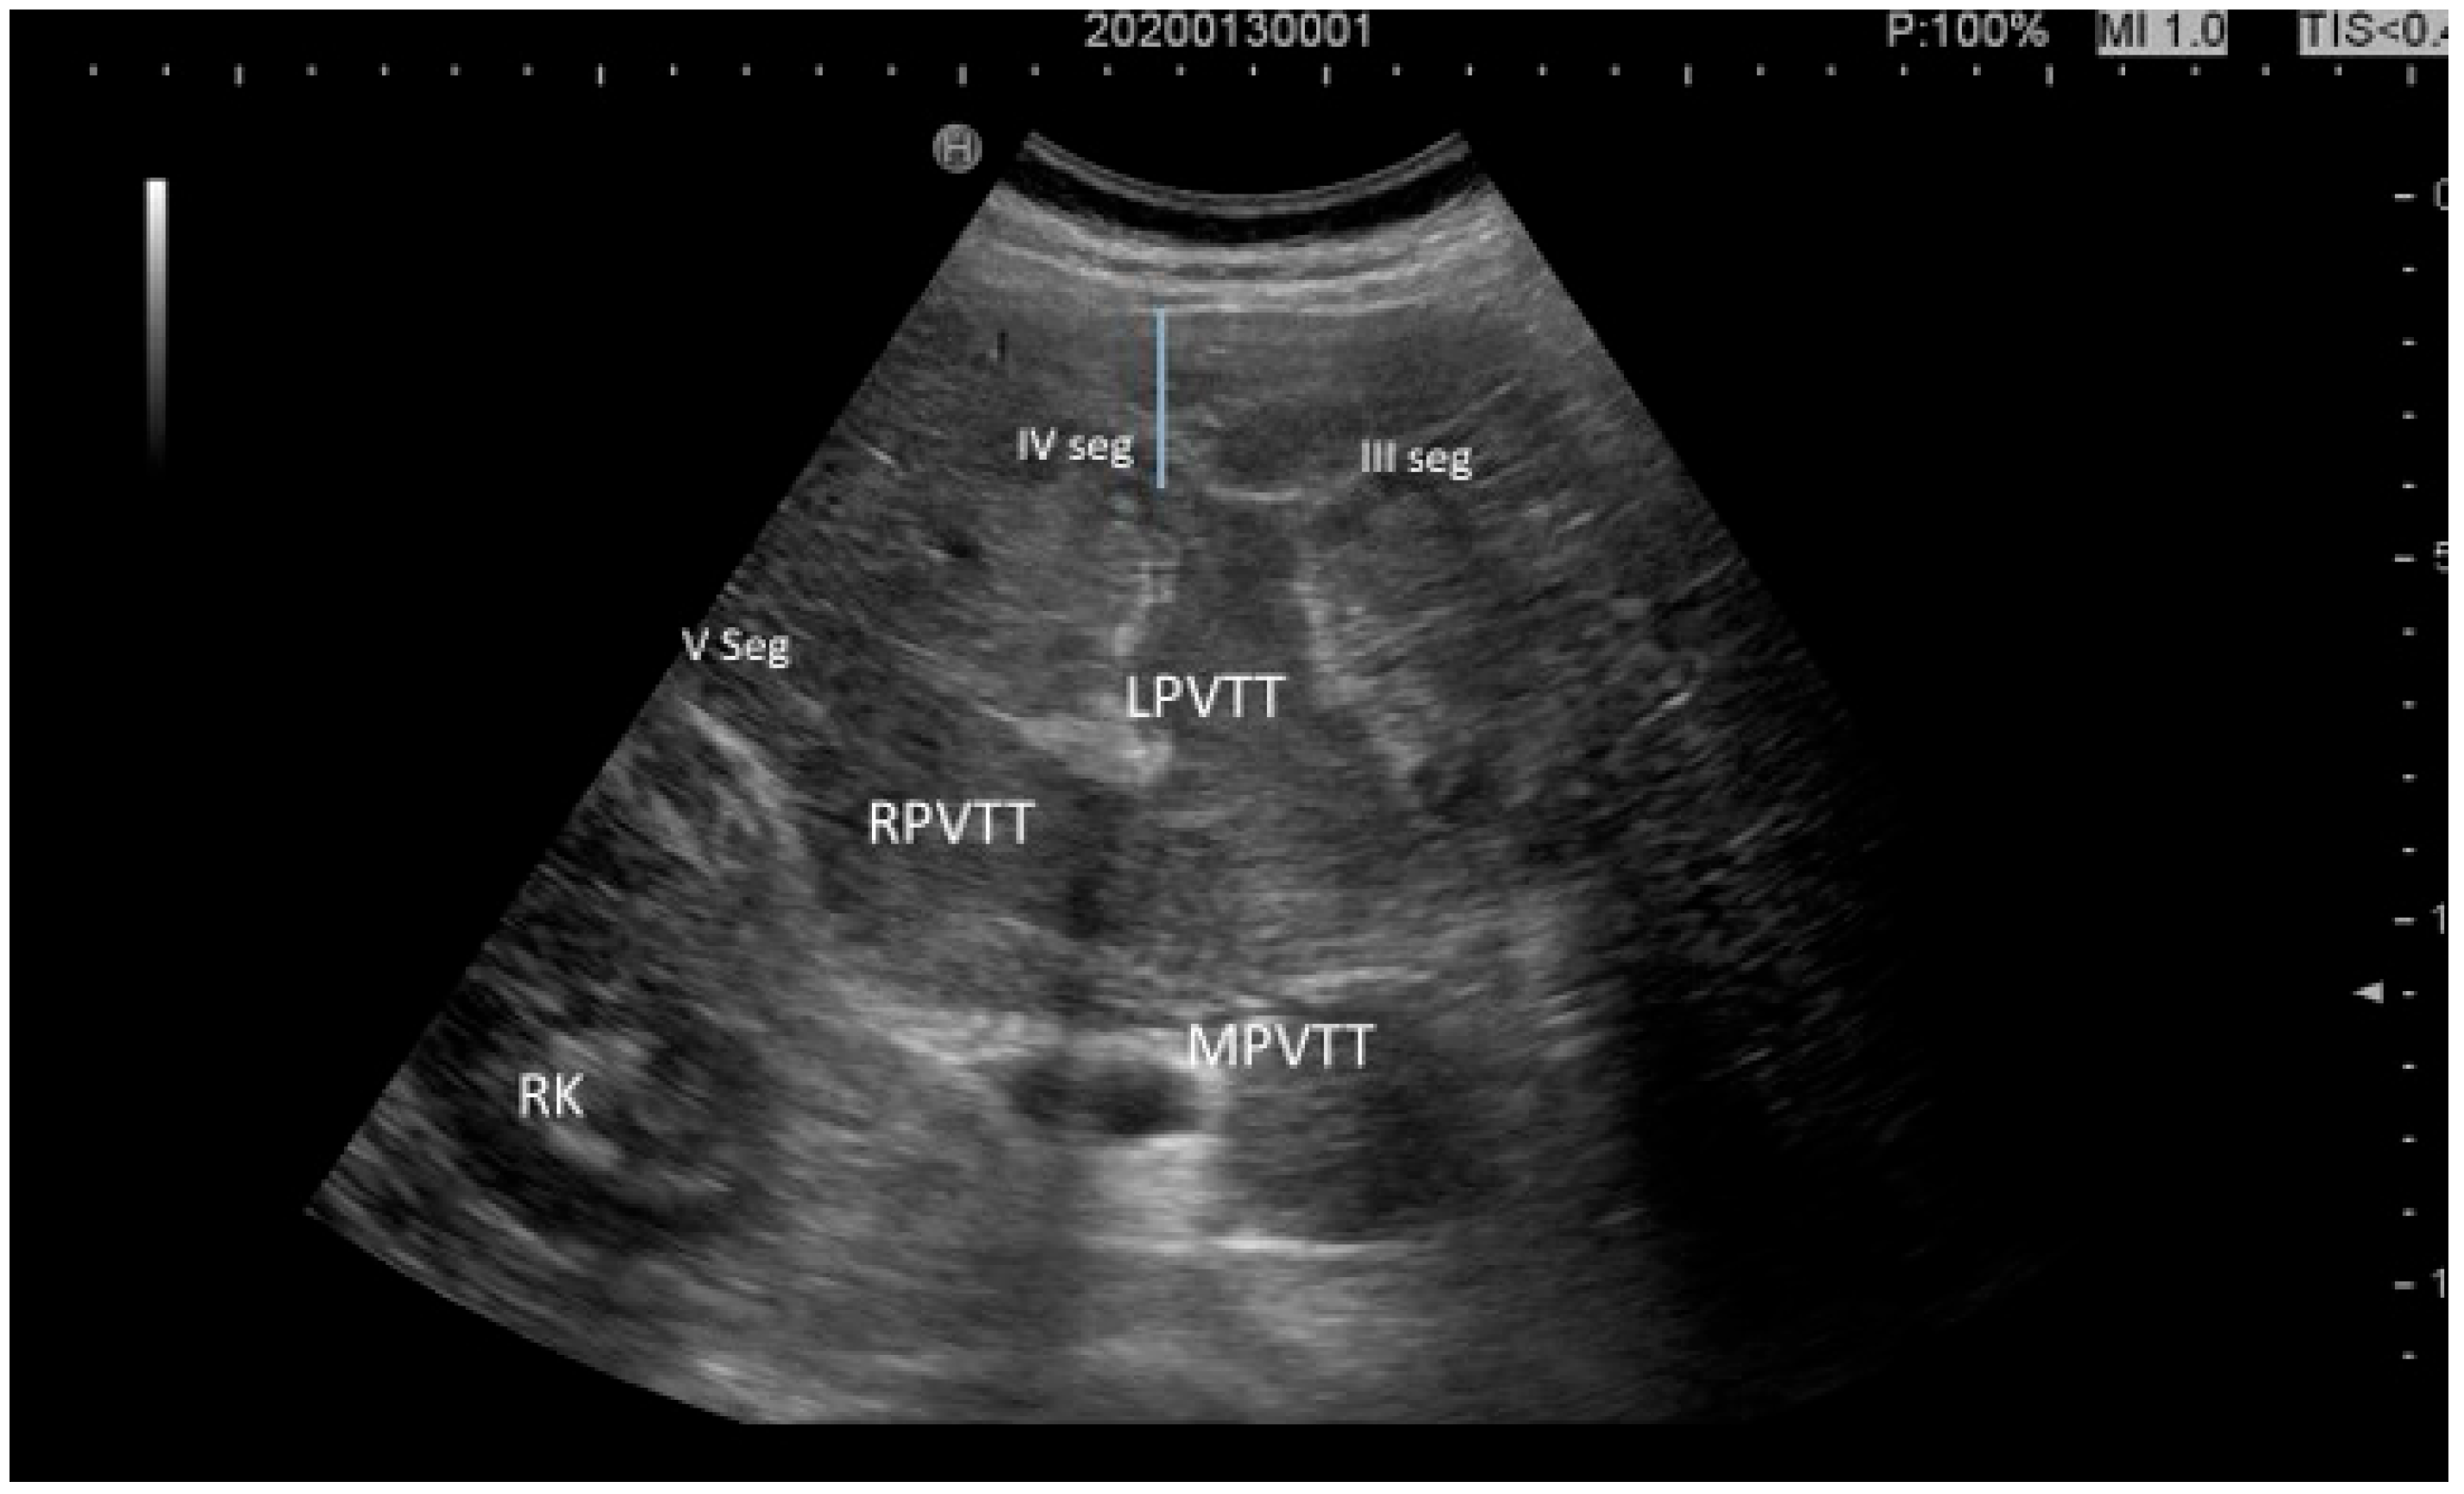

| CEUS LR-TIV (tumor in vein) |

|